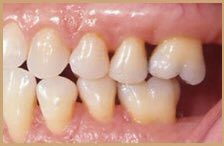

اللثة السليمة:

لكي نتعرف على اللثة المريضة يجب أولا معرفة الصحية أو السليمة ونعرف الاختلافات البسيطة بين جميع الأعراق.

اللثة السليمة لونها زهري(غالبا)ملتصقة بالأسنان لامعة (غالبا)لا تنزف عند اللمس أو التفريش أو بدون سبب/بعض الناس(الملونين)لديهم تصبغات سمراء طبيعية(الشرح لاحقا)(٢)